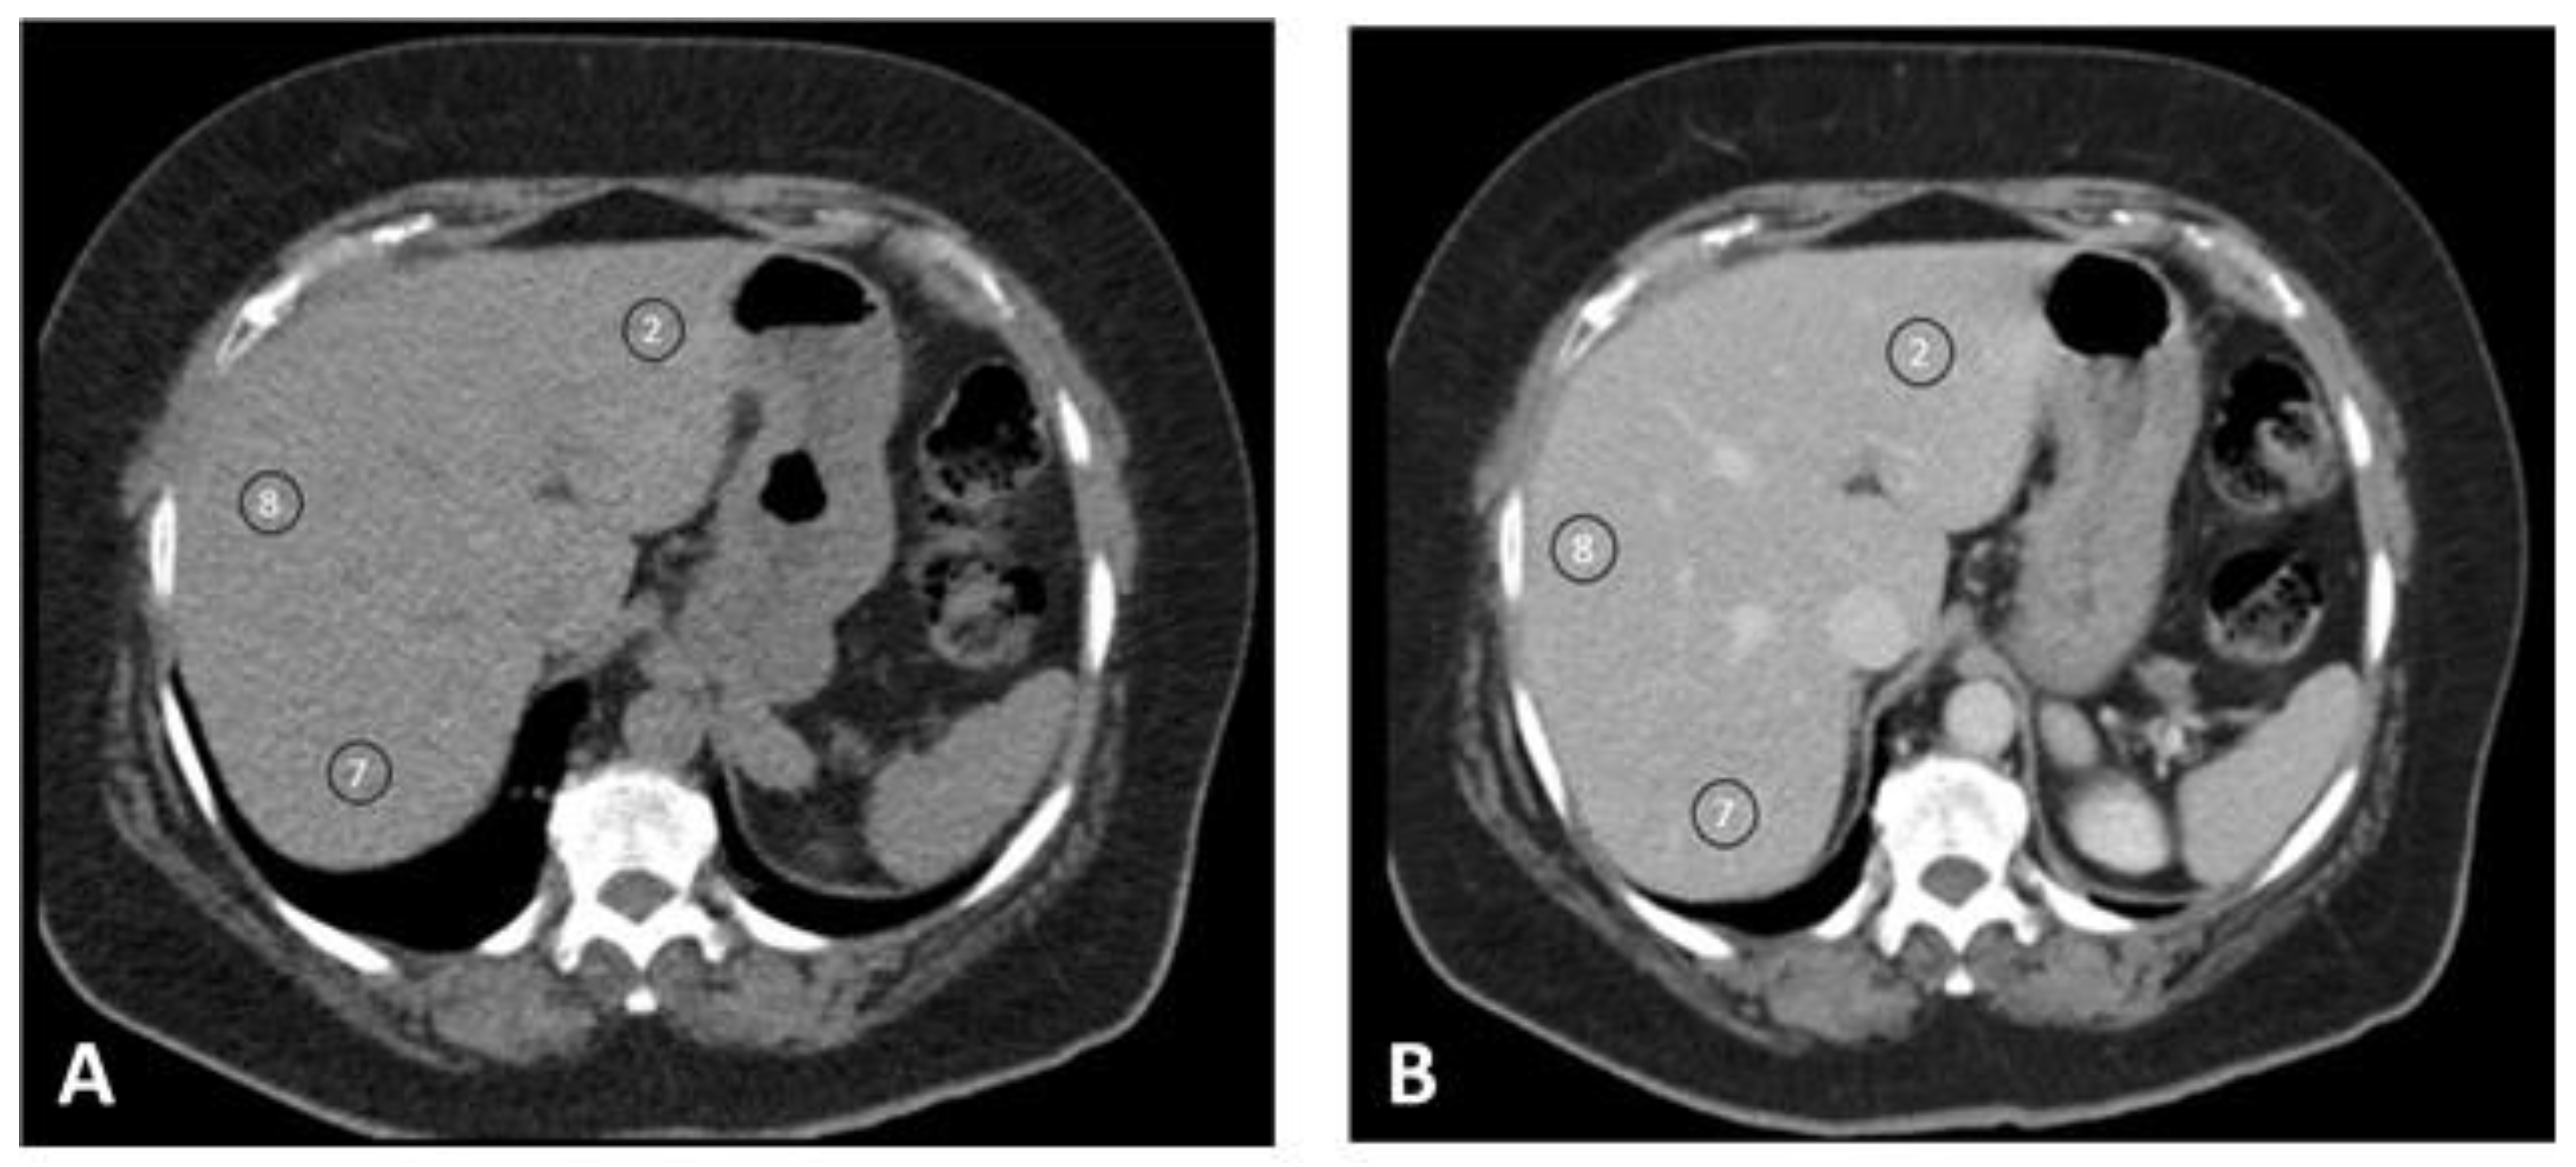

| S2 blanco | 60.5 (±5.77) | 56.7 (±5.02) | 53.6 (±6.30) | 56.8 (±5.83) | 0.000 |

| S2 PV | 120.6 (±11.6) | 109.8 (±11.7) | 105.7 (±9.86) | 111.1 (±12.3) | 0.000 |

| Δ S2 | 60.0 (±10.6) | 53.1 (±10.7) | 52.1 (±6.73) | 54.3 (±10.3) | 0.014 |

| S8 blanco | 60.7 (±5.24) | 55.7 (±5.84) | 51.0 (±6.61) | 55.7 (±6.61) | 0.000 |

| S8 PV | 120.9 (±14.2) | 109.2 (±10.9) | 104.4 (±9.52) | 110.5 (±12.5) | 0.000 |

| Δ S8 | 60.1 (±12.6) | 53.5 (±10.8) | 53.4 (±8.18) | 54.8 (±10.9) | 0.043 |

| S7 blanco | 59.5 (±5.56) | 54.5 (±5.35) | 50.8 (±6.82) | 54.7 (±6.32) | 0.000 |

| S7 PV | 118.7 (±10.8) | 107.8 (±10.1) | 103.1 (±8.34) | 109.0 (±11.1) | 0.000 |

| Δ S7 | 60.1 (±12.6) | 53.3 (±9.25) | 52.4 (±7.45) | 54.3 (±9.30) | 0.022 |

| Mean Δ | 60.7 (±12.4) | 53.3 (±9.75) | 52.6 (±6.63) | 54.6 (±10.2) | 0.007 * |